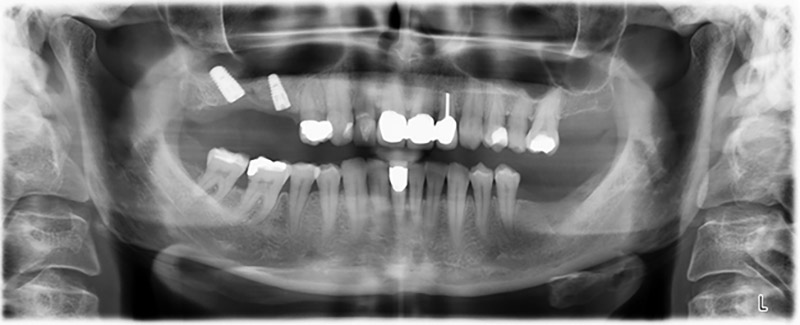

59-годишна пациентка с напреднал стадий на пародонтит описва неприятно чувство и лош вкус в първи квадрант в дисталната зона. Клиничният преглед разкрива силно уголемени пародонтални джобове и напреднала костна атрофия в зона 16 и 14. Рентгенографията потвърждава констатациите (Фиг. 1). Зъби 16 и 14 не могат да бъдат запазени.

Шест месеца след екстракцията на зъби 16 и 14 се извършва преглед с дигитален томограф (DVT, Planmeca), с цел планиране и намаляване на възможните рискове. Ясно се вижда, че костта не се е регенерирала до желания обем (Фиг. 2 до 7).